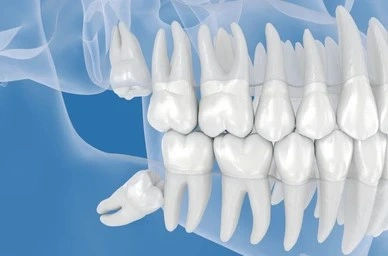

Wisdom teeth are the last set of molars to erupt, often when there isn’t enough space left in the jaw. This lack of space leads to:

Impacted Wisdom Teeth: Teeth trapped in the gums or jawbone.

Angled Eruption: Growing sideways and pushing against nearby teeth.

Partial Eruption: Teeth breaking through the gums only partially, making them prone to infection.

As wisdom teeth push forward, they can crowd the front teeth, especially the lower incisors. This is why some people notice crooked teeth after wisdom tooth eruption.Pressure on Jaw & Gums